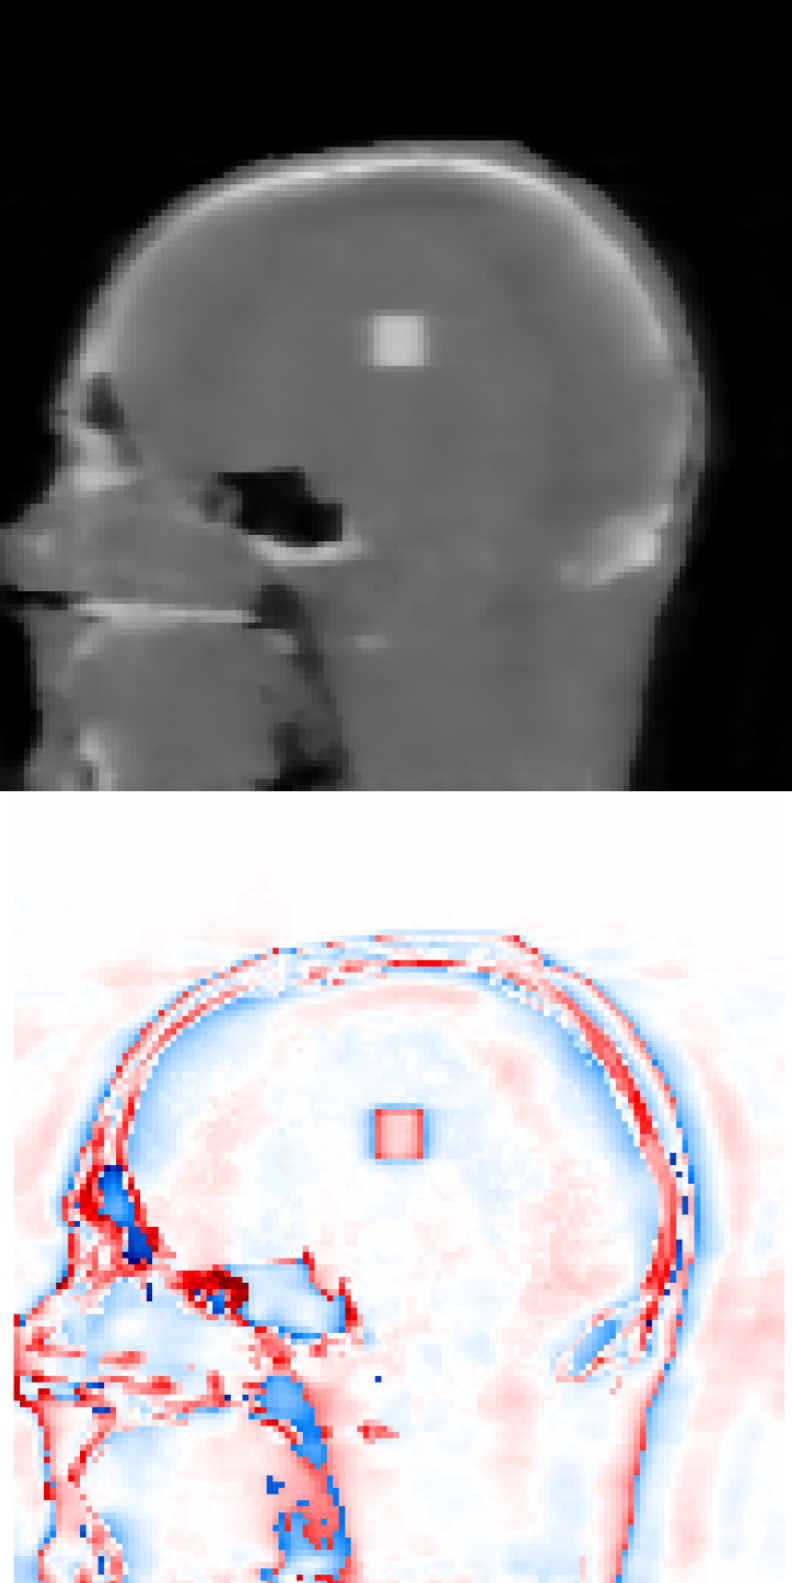

3.1 Digital Head Phantom

In this synthetic example we consider cases where we want to assess if potential tumours have appeared (or changed in size or shape), using a very low number of projections, and we report reconstruction accuracy and computational time for different choices of regularization and optimization algorithm. In particular, we consider a digital head phantom, of size 128×128×128128\times 128\times 128 voxels, with a (synthetically) added cubic tumour of 8×8×88\times 8\times 8 voxels. The DRRs projections were computed in TIGRE with resolution 128×128×20128\times 128\times 20 projections. Note that this is a heavily undersampled dataset: we only consider 20 projections in each imaging step, while a standard clinical scan would require on the order of 600 projections. Even if this is a simple example, i.e. it is highly unlikely to observe a cubic tumour in practice, we believe this to be a highly illustrative test scenario, in which we can both asses the reconstruction quality of the fine structure in the digital head phantom, as well as the edges of the tumour.

For all the algorithms including prior image regularization, the head phantom image without the tumour was used as prior image. This is a reasonable choice, since we know we can do a high-dose scan once and obtain a very accurate reconstruction. Moreover, since this is a synthetic example, we can use the true solution as the ground truth image in our quantitative analysis.

Figure 1 exhibits a slice of the reconstructed images using all the aforementioned algorithms. Here, (a) is the prior image 𝒙p\boldsymbol{x}_{p}, (f) is the ground truth, and the rests are the reconstructed images (top) with the corresponding reconstructions errors (bottom), all displayed using the same colorbar. Note that the error is just the difference between the reconstruction with respect to the ground truth image, so that high pixel intensity indicates inaccurate reconstructions and a fully black image would indicate a perfect reconstruction. This local error information is more informative than only displaying the error norms, or global error, since one can easily observe there is a high local difference between reconstructions.

In terms of global information, Table 1 contains the required number of iterations, reconstruction time, and the different image quality metric scores for the reconstructed images. Moreover, Figure 2 shows the relative error norm histories corresponding to the different reconstruction algorithms.

Since this is a very undersampled dataset, FDK performs qualitatively poorly. Also for SIRT, and IRN-TV the quality drops significantly. The ASD-POCS-TV and ASD-POCS-PICCS are performing well, although a lot of texture information from the image is lost due to the smoothing process. However, the reconstruction time is higher than the other algorithms. The proposed algorithms perform better considering the available texture detail and the reconstruction time. Especially, the image in figure 1(h), IRN-PIPLE, is reconstructing the tumour better by preserving the texture information. Moreover, in figure 1(i), the tumour is more prominently visible due to the added TV regularization in the IRN-PICCS algorithm, however, with compromised original texture information of the image. Note that, for both proposed algorithms, the reconstruction time is in the range of 13 to 76 seconds only.

Figure 1: Reconstructed images using the digital head phantom data, with heavily undersampled projections (20 angles per set). The reconstructed images are shown in [0, 1]; difference images in [–0.5, 0.5].